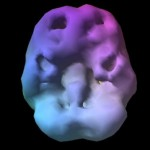

Brain map pri tem tipu pokaže povišano počasno možgansko valovanje med koncentracijo v prefrontalnem predelu in bazalnih ganglijih.

Brain map pri tem tipu pokaže povišano počasno možgansko valovanje med koncentracijo v prefrontalnem predelu in bazalnih ganglijih. Ravno bazalni gangliji so strukture globoko v možganih, ki so zadolžene za produkcijo dopamina.